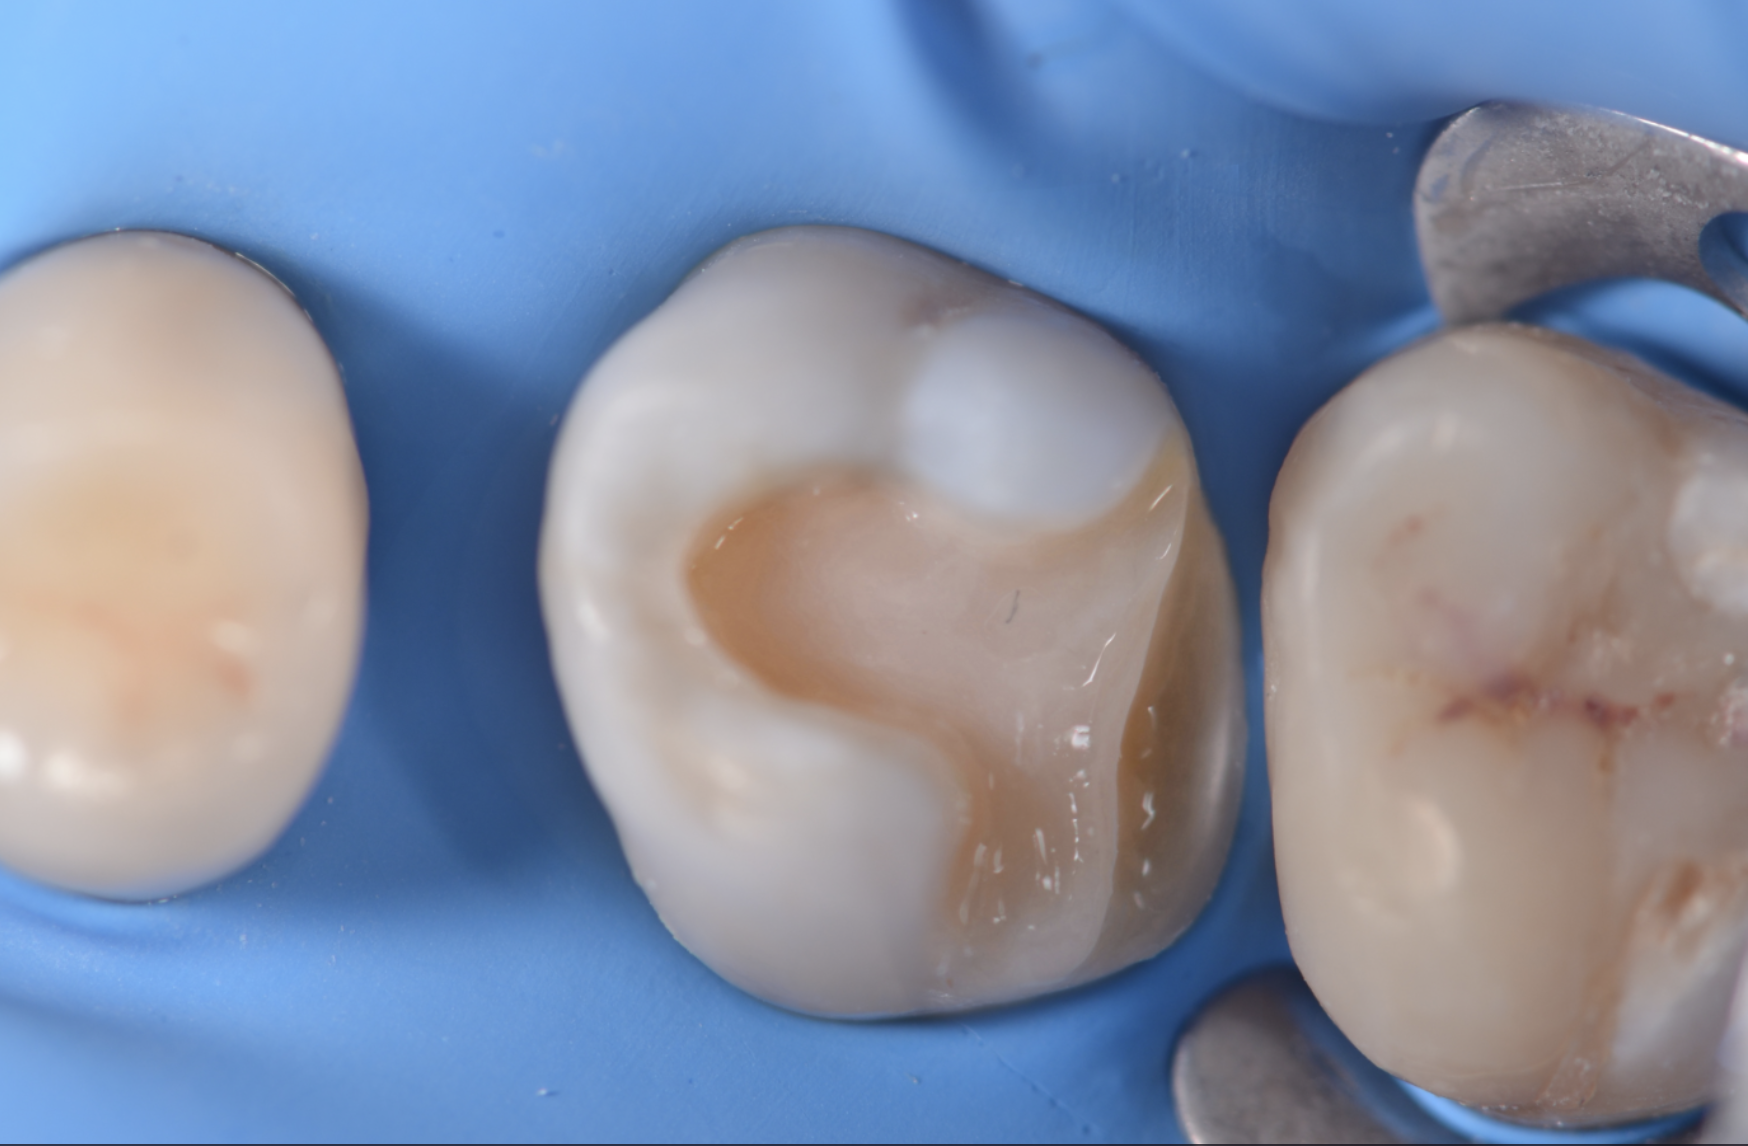

Una paziente di 44 anni si presenta alla nostra attenzione per la sostituzione di un vecchio restauro danneggiato. All’esame clinico si osserva la frattura della cuspide disto-palatina dell’elemento 1.6, associata a infiltrazione marginale di un restauro in composito incongruo. Le radiografie periapicali non evidenziano radiotrasparenze periapicali, ma mostrano possibili aree di demineralizzazione in zona marginale e all’interfaccia dente-restauro (1, 2, 3) (Figure 1-2).

Build-up e rilocazione del margine

Dopo la fotopolimerizzazione (20 secondi), si applica un primo strato di composito flowable bulk (Brilliant Bulk Fill, Coltene, Altstätten, Svizzera) seguendo il protocollo dell’Immediate Dentin Sealing (IDS) (5, 6).

La rilocazione del margine viene eseguita mediante un build-up periferico con composito opaco (7, 8) (Brilliant, Coltene, Altstätten, Svizzera).